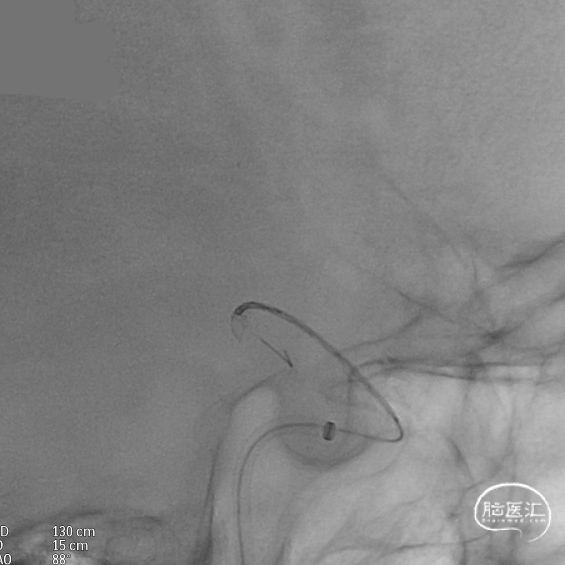

支架到位,远端打开(正侧位):4.75-20mm支架在大脑中动脉M1段打开,回撤至C6段远端锚定。支架释放过程中,轻柔推送支架系统,可见支架导管沿血管壁大弯侧走行,支架打开良好。